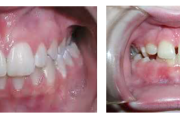

Esimese jäävmolaari ektoopiline lõikumine